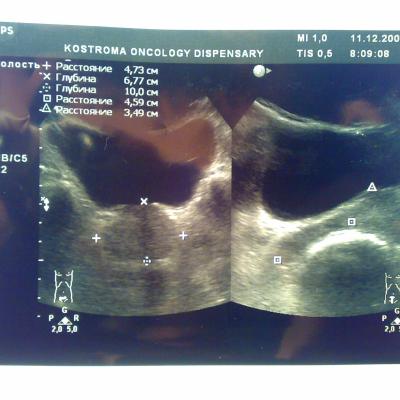

Доброго времени суток. В начале декабря сходил в банное заведение, употребил там пиво, вечером был сексуальный контакт с постоянной партнершей, на утро у обоих появилось жжение при мочеиспускании, у меня покраснение губок полового члена, умеренные выделения прозрачные, анализы крови и мочи в норме, ПЦР у обоих отрицательные. У девушки соэ 28, лейкоциты в моче выше 200, у меня все в норме, бак посев отделяемого из уретры выявил обильный рост Ешерихии коли, принимал внутремышечно Цефотаксим по 1г 2раза в день в течении 5 дней, во время лечения появилось жжение и дискомфорт в промежности. Трузи показало увеличение простаты, расширенные семенные пузырьки около 3 мм, кальцинатов и инфильтратов нет, в область мочевого пузыря не вдается, остаточное количество мочи около 10 мл, кол лейкоцитов в отделяемом из уретры 5-8 в поле зрения. Сейчас принимаю по назначению уролога Нолицин 400 мг по таблетке два раза в день, Палин 250 мг по 1 два раза и азитромицин 250 по одной раз в сутки, свечи на ночь Простатилен курс на 10 дней, уже прошло восемь массажей улучшение незначительное, симптомы в обшей картине сохраняются, железа со слов уролога стала более упругой и меньших размеров. У меня стала страдать эрекция, полной уже нет около 2 месяцев. После эякуляции хочется мочится, неприятные скребущиеся ощущения в промежности, сперма раньше выстреливала, а сейчас вытекает, выстреливает только первая порция, появились боли в мошонке слева, особенно после массажа, подскажите пожалуйста что делать, как лечится, какие еще анализы сдавать. Прикреплены снимки узи.Заранее благодарен.